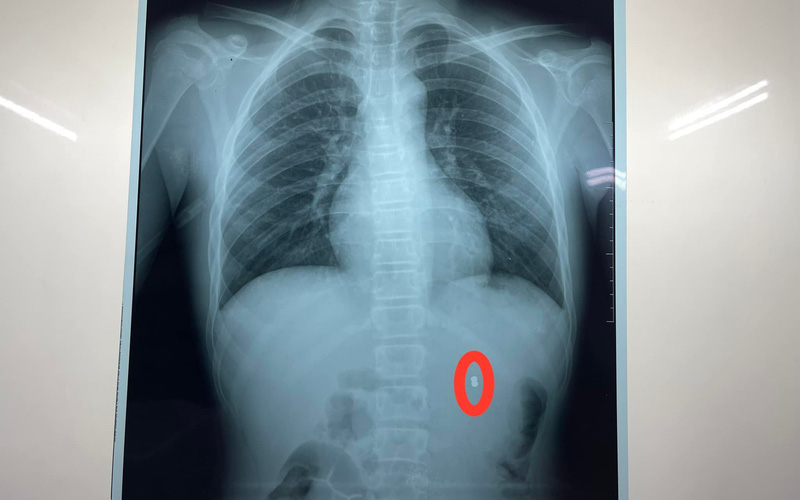

Sau khi được siêu âm, chụp CT bụng có cản quang, phát hiện dị vật hình viên đạn trong thận trái, bệnh nhân được chuyển đến Khoa Ngoại thận tiết niệu nam học. Các bác sĩ đã nhanh chóng hội chẩn và kết luận: bệnh nhân có vết thương thận trái cho đạn bắn, chỉ định mổ cấp cứu lấy dị vật và khâu bảo tồn thận.

Ê-kíp phẫu thuật đã thực hiện rạch vết thương thận, lấy viên đạn súng hơi ra ngoài, khâu cầm máu vết thương, làm sạch khoang quang thận, đồng thời, truyền 500ml máu trong cả quá trình phẫu thuật. Ca phẫu thuật diễn ra thành công sau 1 giờ đồng hồ, đầu đạn chì kích thước 0,4×0,7cm đã được lấy ra ngoài.